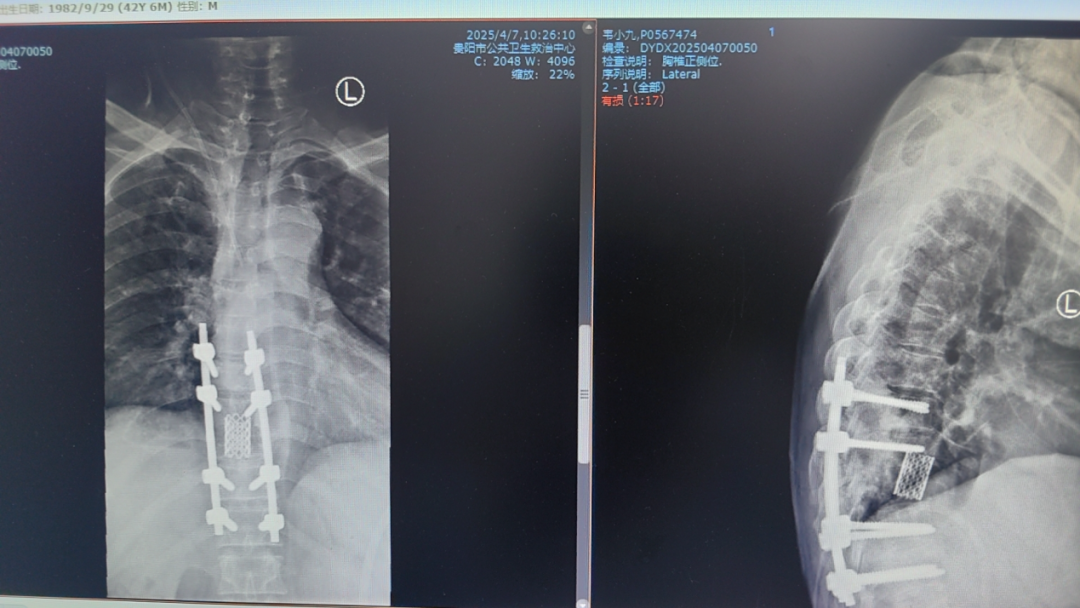

以為是干活勞累,卻突發(fā)癱瘓 “我以為是最近做活路太累了,導(dǎo)致的腰酸背痛,哪曉得突然就癱了!真的感謝周醫(yī)生他們的幫助,把我救回來(lái)了!”談起這番經(jīng)歷,張先生仍心有余悸。 據(jù)悉,今年三月初,42歲的張先生(化名)因胸背疼痛一個(gè)月未進(jìn)行相關(guān)治療,伴隨疼痛進(jìn)行性加重后,入院前3天出現(xiàn)雙下肢無(wú)力、不能行走、大小便失禁等情況。入院時(shí),體查其雙下肢肌力為0,自肋弓以下喪失知覺(jué),無(wú)法坐立,且影像學(xué)檢查顯示,其胸椎上段被結(jié)核性膿腫及壞死骨嚴(yán)重壓迫,脊髓持續(xù)受損。 "每耽誤一分鐘,神經(jīng)壞死風(fēng)險(xiǎn)就增加一分?;颊吣茉僬酒饋?lái)的可能也就減少一分,對(duì)患者家庭是災(zāi)難性后果,我們必須為他爭(zhēng)取時(shí)間。"貴陽(yáng)市公共衛(wèi)生救治中心外三科副主任周波告訴記者;通常情況下,脊柱結(jié)核手術(shù)需2-3周抗結(jié)核治療后再行手術(shù)。但面對(duì)張先生不斷惡化的脊髓損傷,他們必須與患者一同與時(shí)間賽跑:打破常規(guī)的急診手術(shù)決策,進(jìn)過(guò)迅速且嚴(yán)謹(jǐn)?shù)臅?huì)診決策后,靜脈給予一次抗癆治療,團(tuán)隊(duì)當(dāng)機(jī)立斷采用"脊柱前后路聯(lián)合"急診手術(shù)為張先生進(jìn)行施救。“我們首先從前路開胸,清除椎體前方膿腫及壞死組織,植入鈦網(wǎng)替代部分椎體功能,由于椎體跳躍性骨質(zhì)破壞,前路固定不牢固,立即行后路手術(shù),通過(guò)椎弓根釘棒系統(tǒng)實(shí)現(xiàn)脊柱三維穩(wěn)定,再次行后路減壓,雙路徑手術(shù)一次性徹底清除病灶,減壓更充分,復(fù)發(fā)幾率更小。 患者術(shù)前X片 患者胸部CT 患者胸椎核磁共振 術(shù)后復(fù)查的X線 該患者在術(shù)后第一天身體感知覺(jué)有較明顯恢復(fù),第5天開始腳趾恢復(fù)活動(dòng),兩周時(shí)肌力恢復(fù)至3級(jí)以上,截至昨日記者在現(xiàn)場(chǎng)目睹,雙腿已經(jīng)可以自主抬放。周波副主任表示,急性脊髓損傷的黃金救治窗口極短,聯(lián)合入路既能快速減壓又確保長(zhǎng)期穩(wěn)定性,這是恢復(fù)超預(yù)期的關(guān)鍵。預(yù)計(jì)一個(gè)月左右,這位患者就能重新自主行走了。 本次手術(shù)團(tuán)隊(duì)的幾位醫(yī)生正在叮囑患者出院后的注意事項(xiàng) 左起:羅善鵬,石頭,周波,左樂(lè) 專家提示: 腰痛≠腰椎勞損 這些信號(hào)要警惕 針對(duì)近年多發(fā)的"腰痛誤診"現(xiàn)象,周主任特別提醒:腰椎結(jié)核多以持續(xù)性腰痛為主,多伴低熱、盜汗、體重下降等結(jié)核中毒癥狀;而腰椎間盤突出典型表現(xiàn)為腿痛腿麻等。一定要注意的是當(dāng)出現(xiàn)腰痛合并下肢無(wú)力、大小便功能障礙時(shí),無(wú)論屬于哪一種情況都需立即就醫(yī)。 據(jù)統(tǒng)計(jì),我國(guó)結(jié)核感染人群超2億,其中5%-10%的肺外結(jié)核可累及脊柱。專家強(qiáng)調(diào),骨結(jié)核雖發(fā)病率低,但致殘率高,早期規(guī)范治療可避免災(zāi)難性后果。 專家簡(jiǎn)介 周波,男,43歲,副主任醫(yī)師,中國(guó)抗癆協(xié)會(huì)結(jié)核病健康促進(jìn)分會(huì)委員,中華醫(yī)學(xué)會(huì)貴陽(yáng)市骨科分會(huì)委員、貴陽(yáng)市康復(fù)醫(yī)學(xué)會(huì)委員,貴陽(yáng)市骨科質(zhì)量委員會(huì)委員,貴陽(yáng)市艾滋病性病防治協(xié)會(huì)委員,中國(guó)中醫(yī)藥信息學(xué)會(huì)骨科分會(huì)委員,從事臨床醫(yī)學(xué)骨外科專業(yè)15余年,擅長(zhǎng)脊柱結(jié)核及其截癱患者的治療,搶救脊髓功能,擅長(zhǎng)骨與關(guān)節(jié)結(jié)核的診治,髖、膝關(guān)節(jié)置換的治療,術(shù)后療效顯著,有效減少患者的致殘率。在國(guó)內(nèi)學(xué)術(shù)核心雜志發(fā)表學(xué)術(shù)專業(yè)文章15篇。